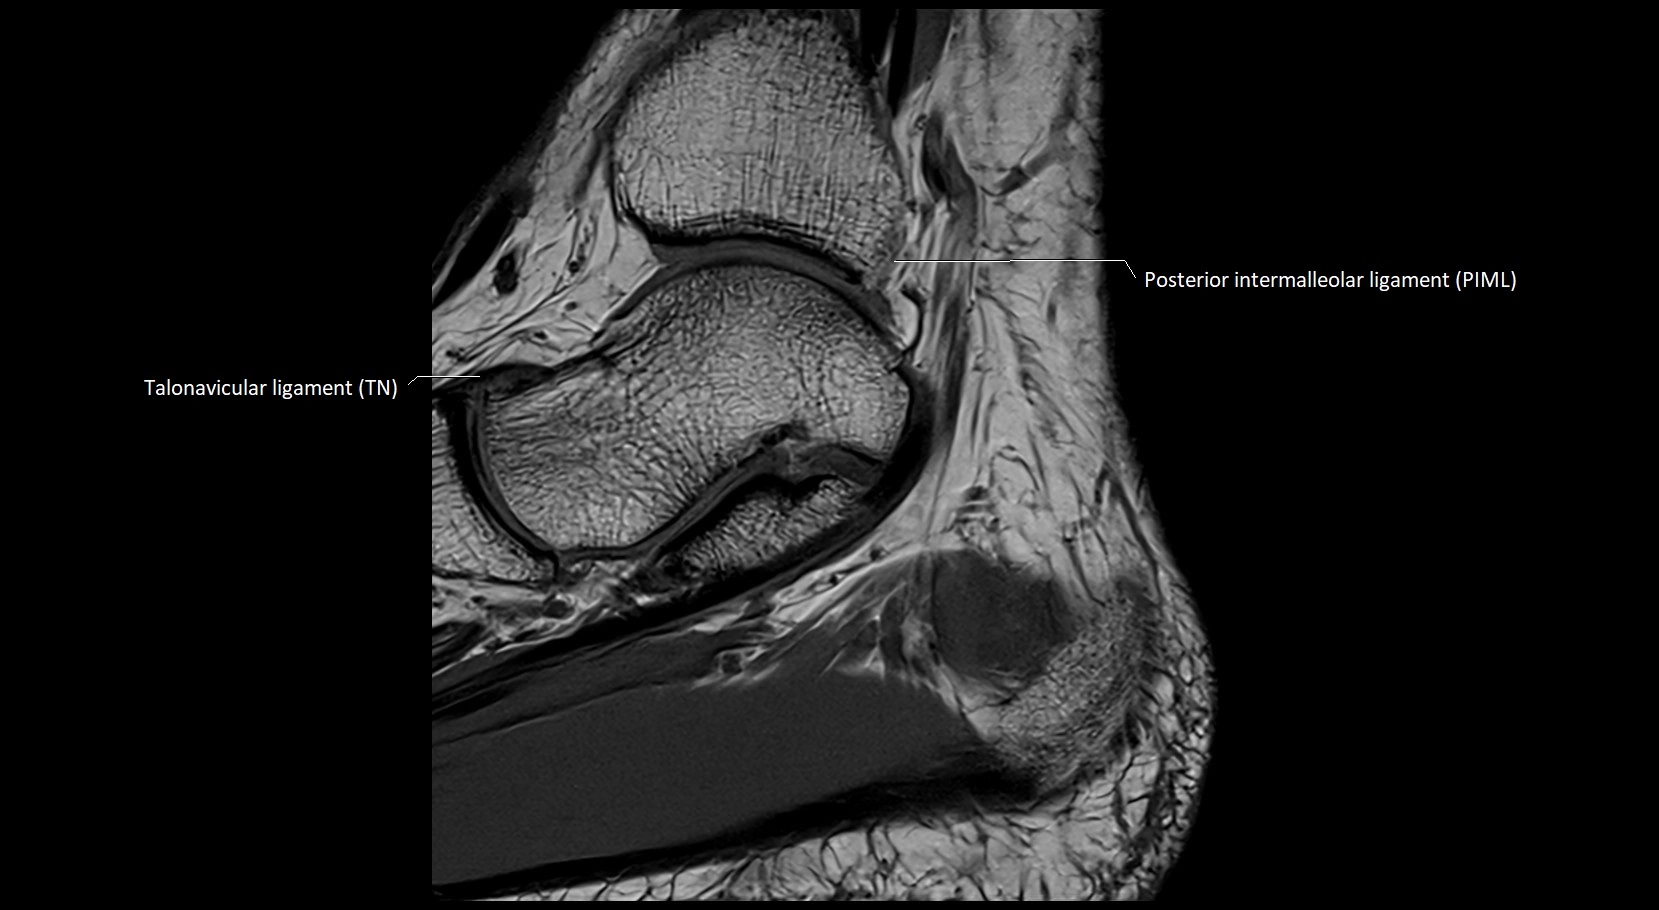

MRI image

image